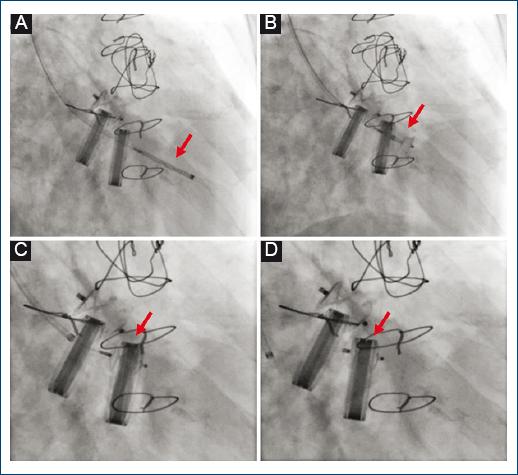

Figure 3 Transcatheter closure of tricuspid paravalvular leak. Amplatzer Vascular Plug II 8/4 mm (red arrows). A: anterograde crossing of the defect from jugular access and advancement of the release system. B: release of occluder initial retaining disc. C: release of occluder final retention disk. D: final result by fluoroscopy.